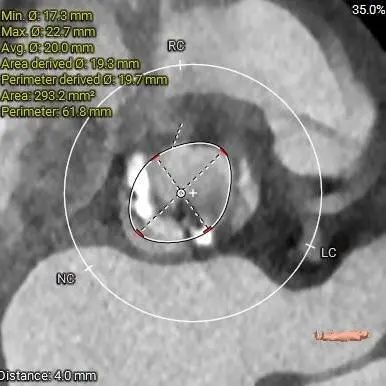

超声提示:峰值流速4.8m/s,跨瓣压差 91mmHg。

主动脉瓣重度狭窄伴轻度关闭不全,左室肥厚。

主动脉根部详细情况:

ANNULUS

三叶式主动脉瓣,瓣叶轻中度钙化并明显增厚,人工瓣膜锚定力尚可,左室流出道呈敞口型,综合多平面分析,预估瓣膜释放后有向下位移风险及瓣周漏可能。

直径20mm TaurusAtlas球囊进行预扩,同时预装TaurusElite AV23瓣膜。瓣环下0-2mm开始定位释放。释放过程中多角度造影,超声辅助定位确定瓣膜最终位置。释放后再次造影确定佐证。